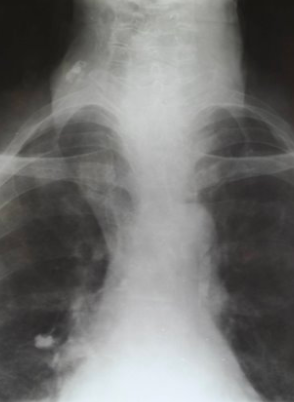

Rx toracică, incidență P-A

DESCRIERE: DAS + stază

indice cardiotoracic ↑

semne de dilatare a AS:

dublu contur inferior drept (contur dublu “festonat“)

deschiderea unghiului de bifurcație a traheei >120 grade

bombarea arcului mijl stg (golful pulm) → HTP

semne de stază pulm: dilatarea hilurilor + apicalizarea circulației + linii Kerley B

DX: stenoză mitrală

DD: insuf mitrală, boală mitrală, stenoză Ao